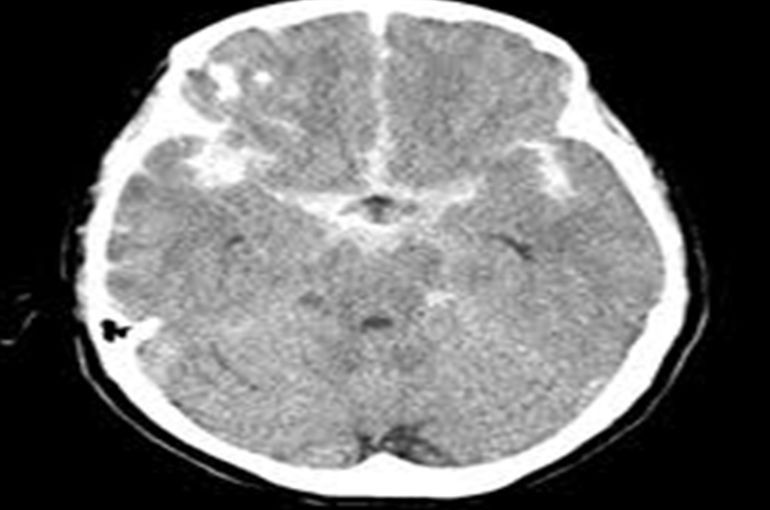

□【くも膜下出血】

くも膜下出血による頭痛の特徴としては、

・金属バッドでなぐられたような痛み

・吐き気や嘔吐を伴う

上記のような頭痛は「くも膜下出血」の可能性があります。

病院でCT検査等を取ることをおすすめします。